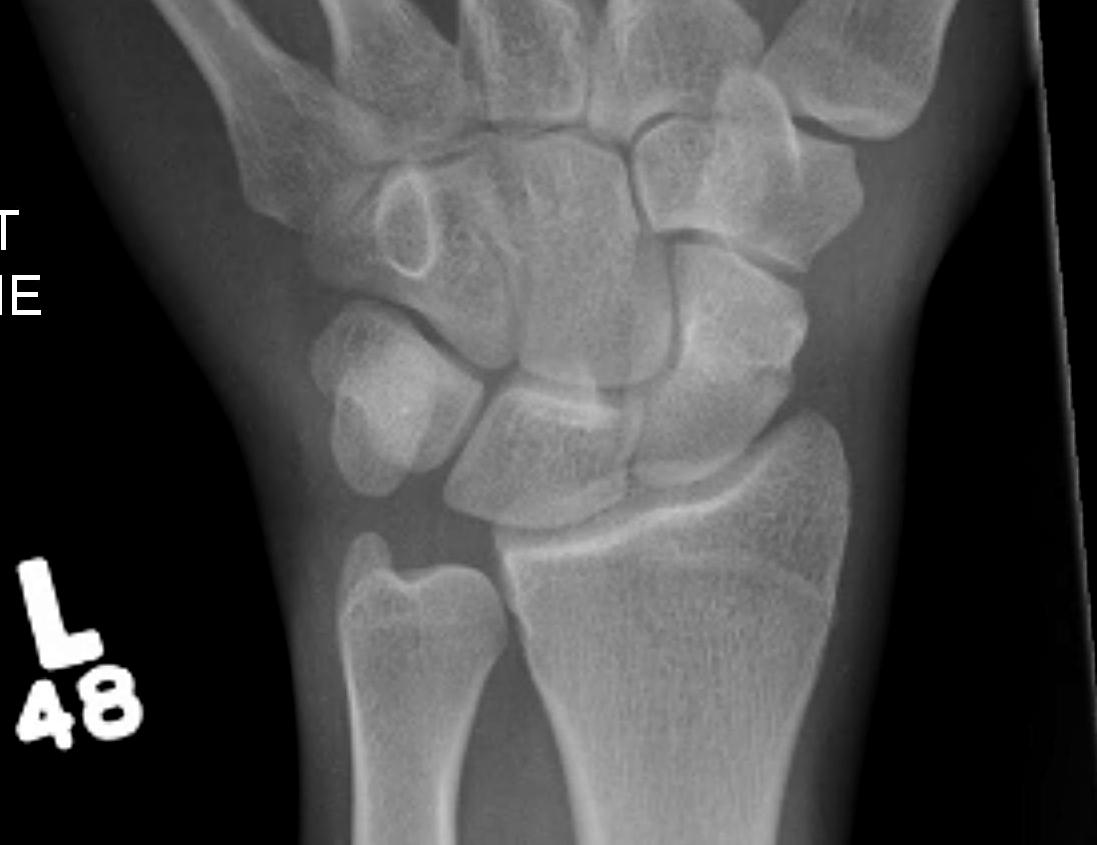

Scaphoid waist fracture 1 mm displaced

Scaphoid fracture with significant displacement

Scaphoid proximal pole fracture